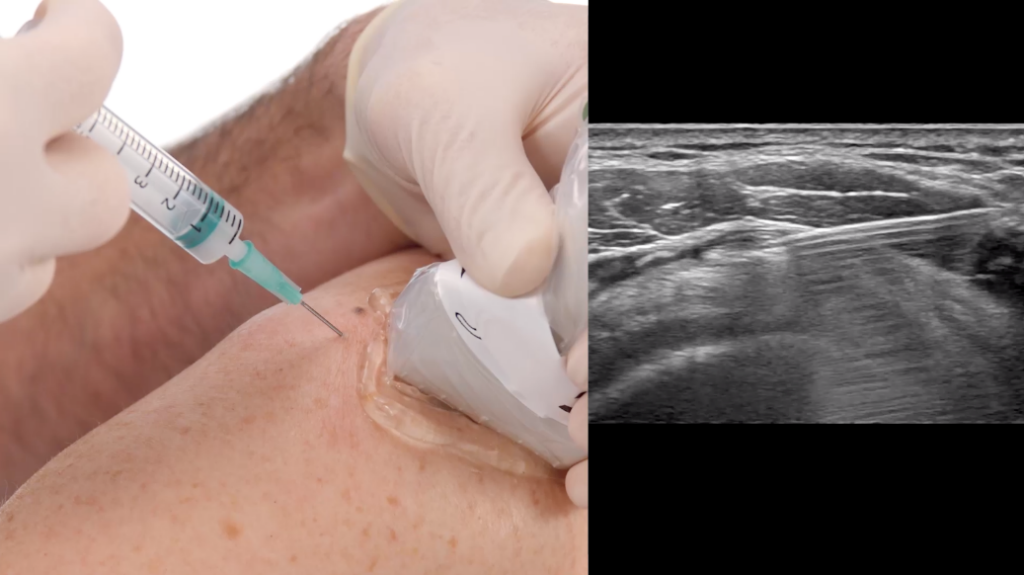

- Ενέσεις στεροειδών στον ώμο

Τα στεροειδή φάρμακα βοηθούν στη μείωση της φλεγμονής.

Η ένεση στεροειδών μπορεί να γίνει με την καθοδήγηση υπερηχογραφήματος ώστε να επιτευχθεί μεγαλύτερη ακρίβεια και ελάχιστος πόνος/ ενόχληση από τη διαδικασία.